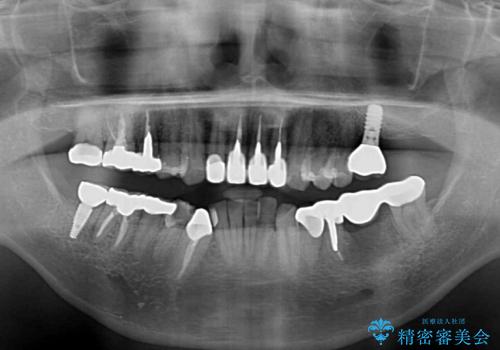

目立つ金属をすべてセラミックに 全顎的メタルフリー治療

欠損している歯や、割れてしまって抜歯の必要な歯などがあり、咬合力が強いため欠損部はインプラント補綴を前提に治療を行うこととしました。

しかしながら、左下の抜歯部位は骨欠損が著しく大きく、多大な垂直的骨造成を要するため、3歯を支台としたブリッジによる補綴治療とし、右下のみをインプラント補綴としました。

小さい修復物の銀歯が装着されている歯はセラミックインレーにて、その他はオールセラミッククラウンにて補綴治療を進めることとしました。